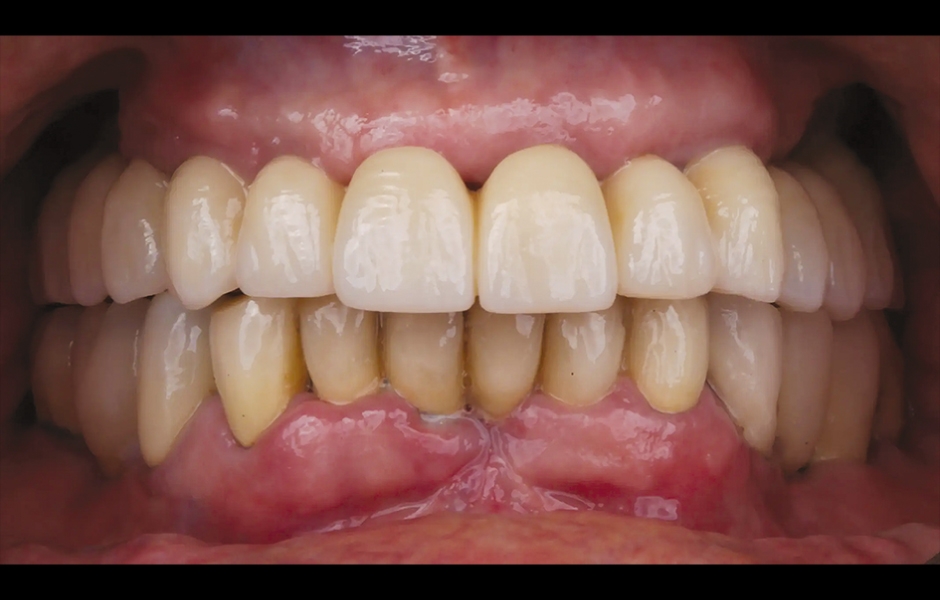

85letý částečně bezzubý pacient byl odeslán na naši kliniku k celkové rehabilitaci horní čelisti. Pacient byl v dobrém celkovém zdravotním stavu a nekuřák. Jeho hlavní stížnosti zahrnovaly obtíže při žvýkání, bolest v horní čelisti a občasný zápach z úst. Klinické a radiologické vyšetření odhalilo krátký fixní metalokeramický můstek nesený sedmi frontálními zuby horní čelisti. Protetická práce se uvolnila a čtyři z pilířových zubů byly strukturálně narušeny. Zbývající tři vykazovaly různé stupně kazivých lézí a parodontálních problémů. Byla stanovena diagnóza selhávající dentice (obr. 1 a 2).

Obr. 1: Výchozí situace, čelní pohled. (Všechny snímky: Dr. Marco Tallarico a kol.).

Obr. 2: Výchozí situace, okluzální pohled.